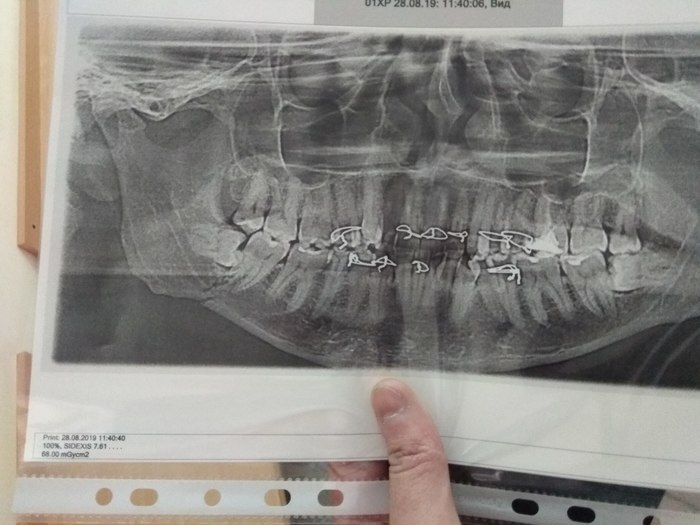

Здравствуйте,не так давно писал о переломе челюсти во время удаления 48 зуба. Прошло с 28 августа,почти 3 недели. Сегодня сделал снимок-

Уже 20 числа предстоит отпуск,как я понимаю шину снимать рано? Ещё ничего не срослось? Придется лететь с шиной.

Помогите советом,когда вообще снимается эта шина?

Врач хотел снимать 14 числа,уверял,что нормально,но потом отказался,сказал,что до 25 оставит.

Сходил на консультацию к другому,сказал,что не менее 5-6 недель ходить.

А так выглядит снимок с шиной